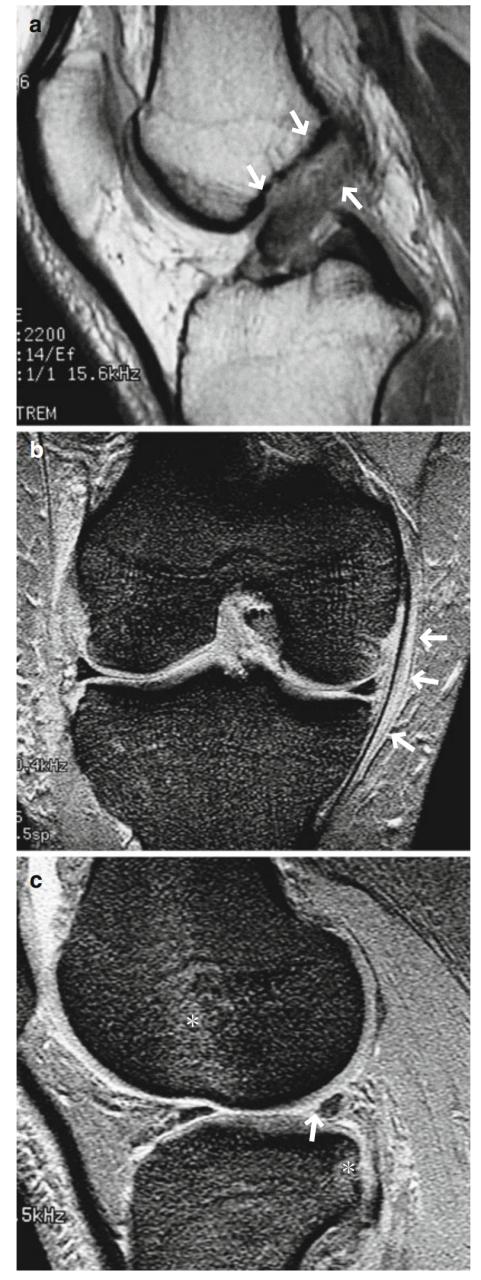

- 与前交叉韧带撕裂相关的半月板撕裂在外侧比内侧半月板更常见。事实上,继发于前交叉韧带撕裂的骨挫伤可见于股骨和胫骨的外侧,相应的撕裂常见于外侧半月板的后段/角(图7.23)。

- 内侧半月板撕裂、前交叉韧带撕裂和MCL撕裂的组合被称为奥多诺休三联征(‘O'Donoghue's triad)。然而,更常见的是外侧半月板撕裂合并前交叉韧带撕裂和MCL撕裂。

- 与韧带撕裂相关的半月板撕裂通常是内侧或外侧半月板后段/角的纵向撕裂。

图7.23外侧半月板撕裂合并前交叉韧带撕裂和MCL撕裂。一个26岁的男性。(a ) PDWI,(b)冠状T2*WI,以及(c ) T2*WI。观察到急性ACL撕裂(箭头,a)和1级MCL损伤(箭头,b)。与这些损伤一起发生半月板损伤通常是外侧的而不是内侧的。外侧半月板后角的纵向撕裂尤其常见(箭头,c)。骨挫伤出现在股骨外侧髁和胫骨平台的后部(*,c)